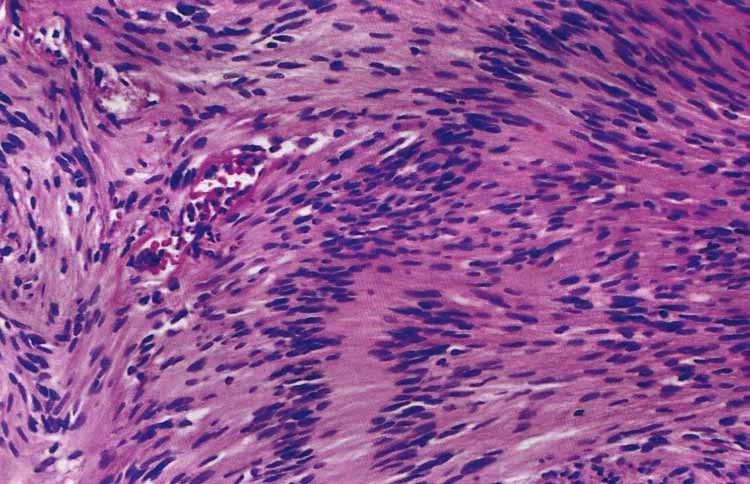

Schwannoma: note the Antoni A (more cellular, palisading nuclei with surrounding pink areas with rows of nuclei in parallel array called Verocay bodies) and Antoni B which has looser stroma, fewer cells, and myxoid change